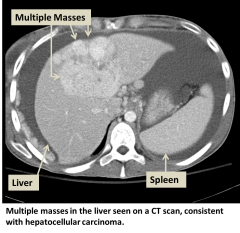

Hepatocellular carcinoma (HCC) is the most common type of primary liver cancer. Primary liver cancer refers to cancer that originates in the liver rather than cancers from other organs that metastasize to the liver (see metastatic liver cancer). HCC can start as a single tumor or as several tumor nodules across the liver.

- CT scan